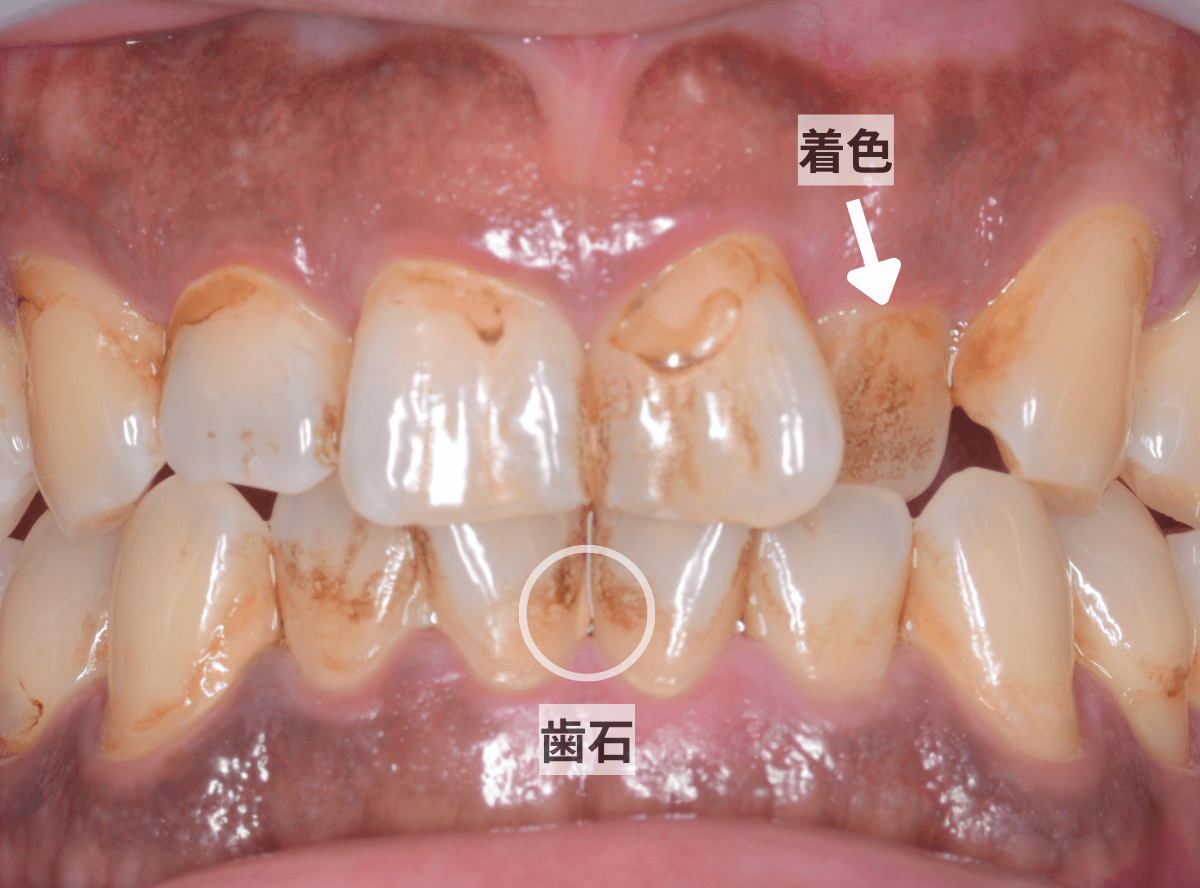

主な着色部位と歯石はこちらです。

歯石を拡大した様子です。

こちらの方は、着色の割には歯石は少量が表面上にとどまっている状態でしたので、時間をお取りしてしっかり歯周辺をクリーニングする「ビューティー・クリーニング:60分 1万円」をご提案し、選択されました。